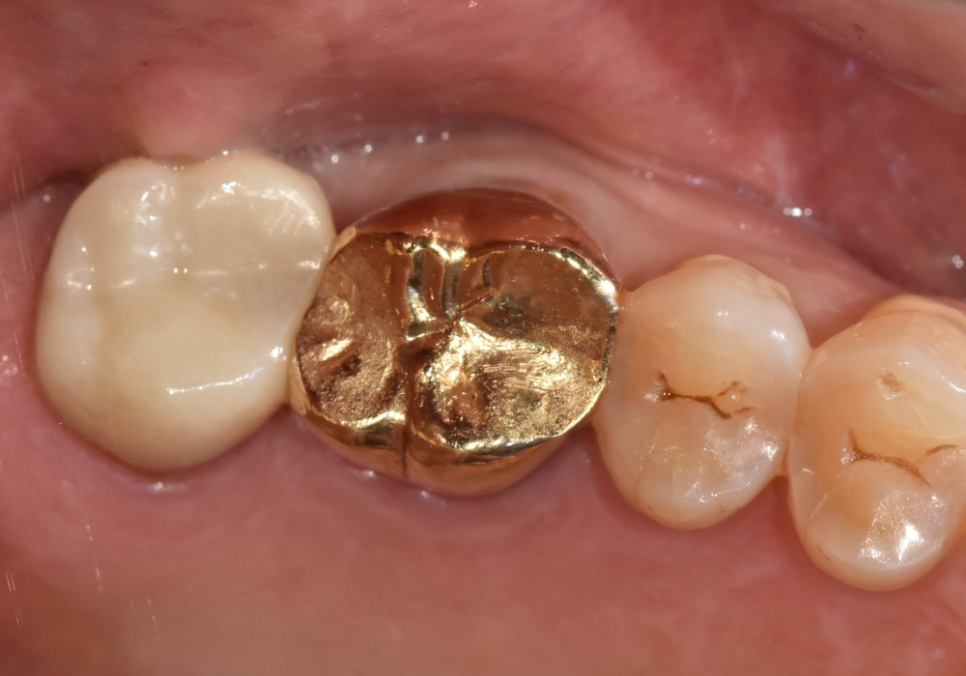

통증이 완전히 사라진 것을 확인한 뒤,

깨끗해진 신경관 안을 생체 친화적인 재료로

단단하게 채워 넣었습니다.

그리고 금이 간 치아가

더 이상 벌어지거나 깨지지 않도록

치아 전체를 감싸주는

크라운 치료를 진행했습니다.

240305

균열이 있는 치아는 크라운으로

단단하게 잡아주는 보강 작업이

무엇보다 중요합니다.